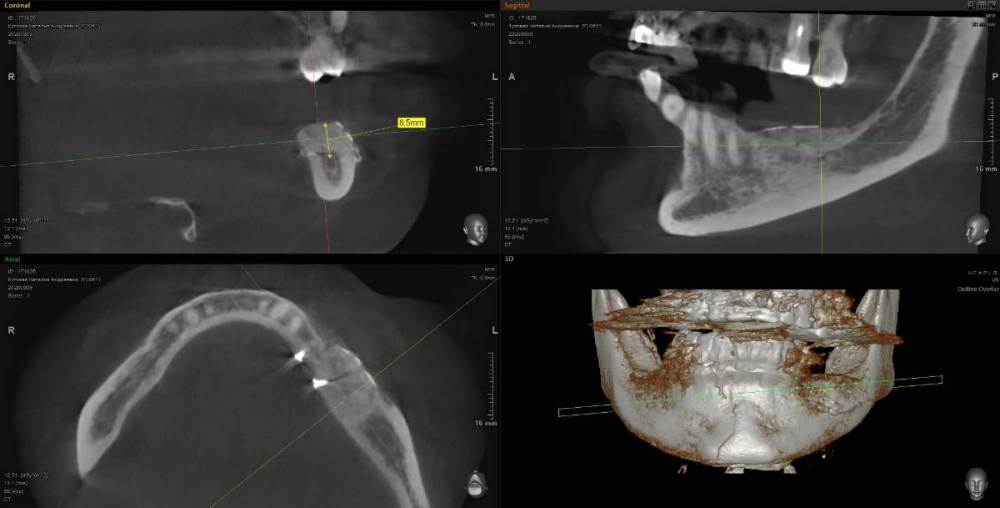

Kostoprav Опубликовано 11 мая, 2021 Поделиться Опубликовано 11 мая, 2021 (изменено) 70%ауто+30% ксено, мембрана цитофлекс, винты самосверлящие после пластики до установки имплантов прошло 8 мес. Изменено 11 мая, 2021 пользователем Kostoprav 3 6 Ссылка на комментарий

Карен Аванесов Опубликовано 12 мая, 2021 Поделиться Опубликовано 12 мая, 2021 20 часов назад, Kostoprav сказал: 70%ауто+30% ксено, мембрана цитофлекс, винты самосверлящие после пластики до установки имплантов прошло 8 мес. Замечательно! 1 Ссылка на комментарий